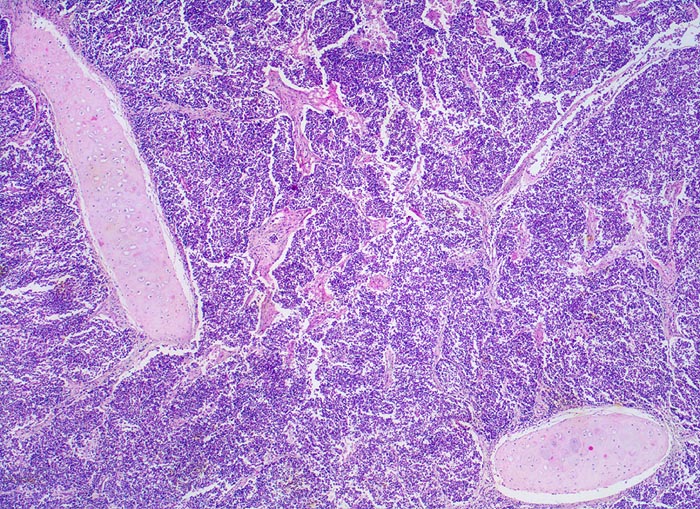

Die monomorphen rundlichen, fusiformen oder polygonalen Tumorzellen haben sehr wenig Zytoplasma, die Kerne sind hyperchromatisch und Nukleolen sind kaum zu erkennen. Die Tumorzellen bilden lockere Verbände, bandförmige Anordnungen oder Pseudorosetten um Gefässe. Oftmals zeigen die Tumoren in der Biopsie charakteristische Quetschartefakte. Ein histologisches Grading wird im Gegensatz zu den nicht kleinzelligen Karzinomen nicht vorgenommen. An kleinen Biopsien kann die morphologische Unterscheidung eines kleinzelligen Karzinoms von einem Lymphom bzw. von normalem lymphatischem Gewebe schwierig sein (> 1101). Diese Unterscheidung gelingt aber meist problemlos mit Hilfe einer immunhistochemischen Zusatzuntersuchung (> 1100).

• Drei Bronchialschleimhautbiopsien ausgekleidet von respiratorischem Flimmerepithel.

• Blauer, sehr zelldichter solider Tumor in der Submukosa des mittleren Biopsiefragmentes. Die beiden anderen Schleimhautfragmente sind tumorfrei.

• Tumorzellen mit sehr schmalem Zytoplasmasaum ("nacktkernig").

• Eckige, ovale oder rundliche Kerne mit uniform feinkörnigem Pfeffer und Salz Chromatin.

• Tumorzellkerne etwa dreimal so gross wie Lymphozytenkerne.

• Nukleolen sind nicht erkennbar oder sehr klein.

• Herdförmig Quetschartefakte (langgezogene Kernschlieren).

• Sehr zahlreiche Apoptosen und kleinherdige Tumornekrosen.

• Perineuralscheideninvasion.